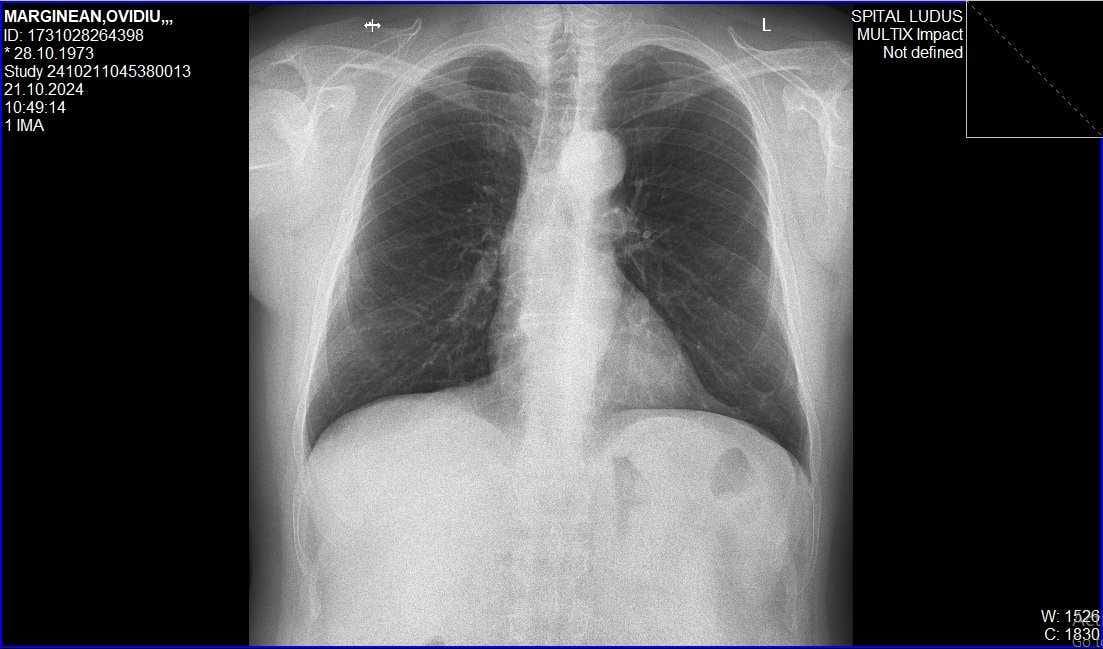

Pneumology hospital

Ludus - Romania

21 Oct. 2024

Lung X-ray,

Diaphragm Disease

Investigation summary:

The diaphragm is flattened and does not function normally.

Attempts are made to restore diaphragm function with specific treatment and exercises.